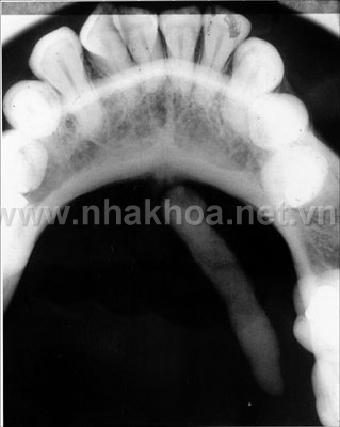

Chẩn đoán xác định bằng cách chụp tuyến nước bọt cản quang, siêu âm tuyến hoặc chụp cắt lớp. Cách điều trị duy nhất là phẫu thuật lấy bỏ tuyến nước bọt, cắt một phần hoặc toàn bộ tùy theo bệnh tích.